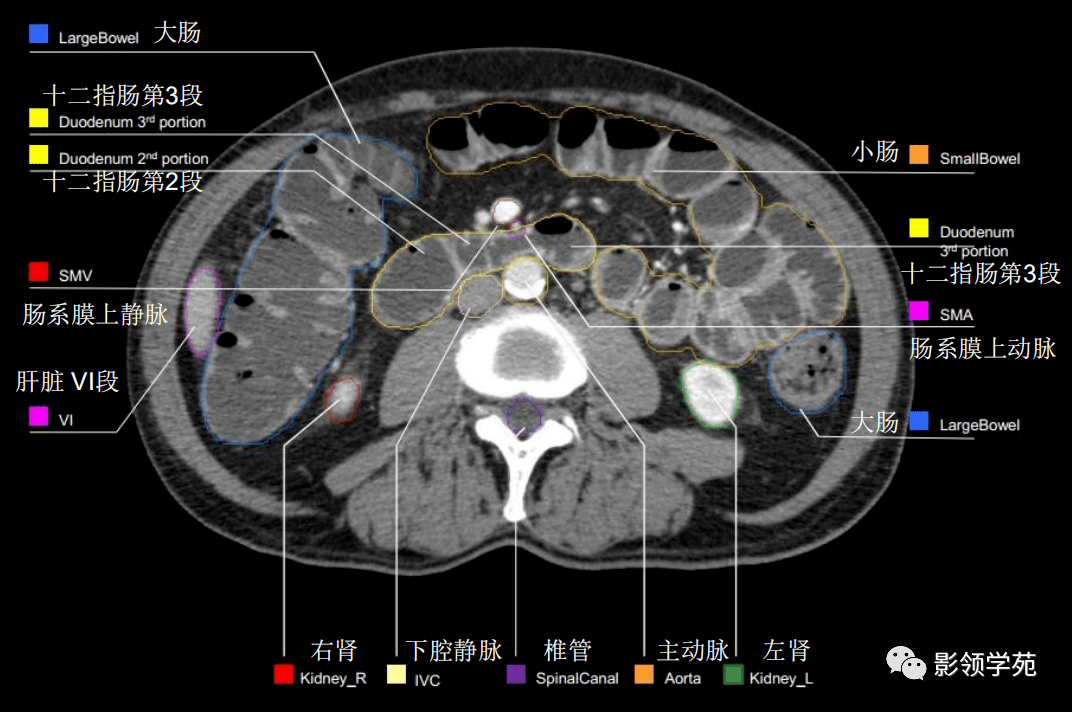

46组对比图带你完全掌握腹部影像解剖_医学界-助力医生临床决策和职业

图片尺寸640x429